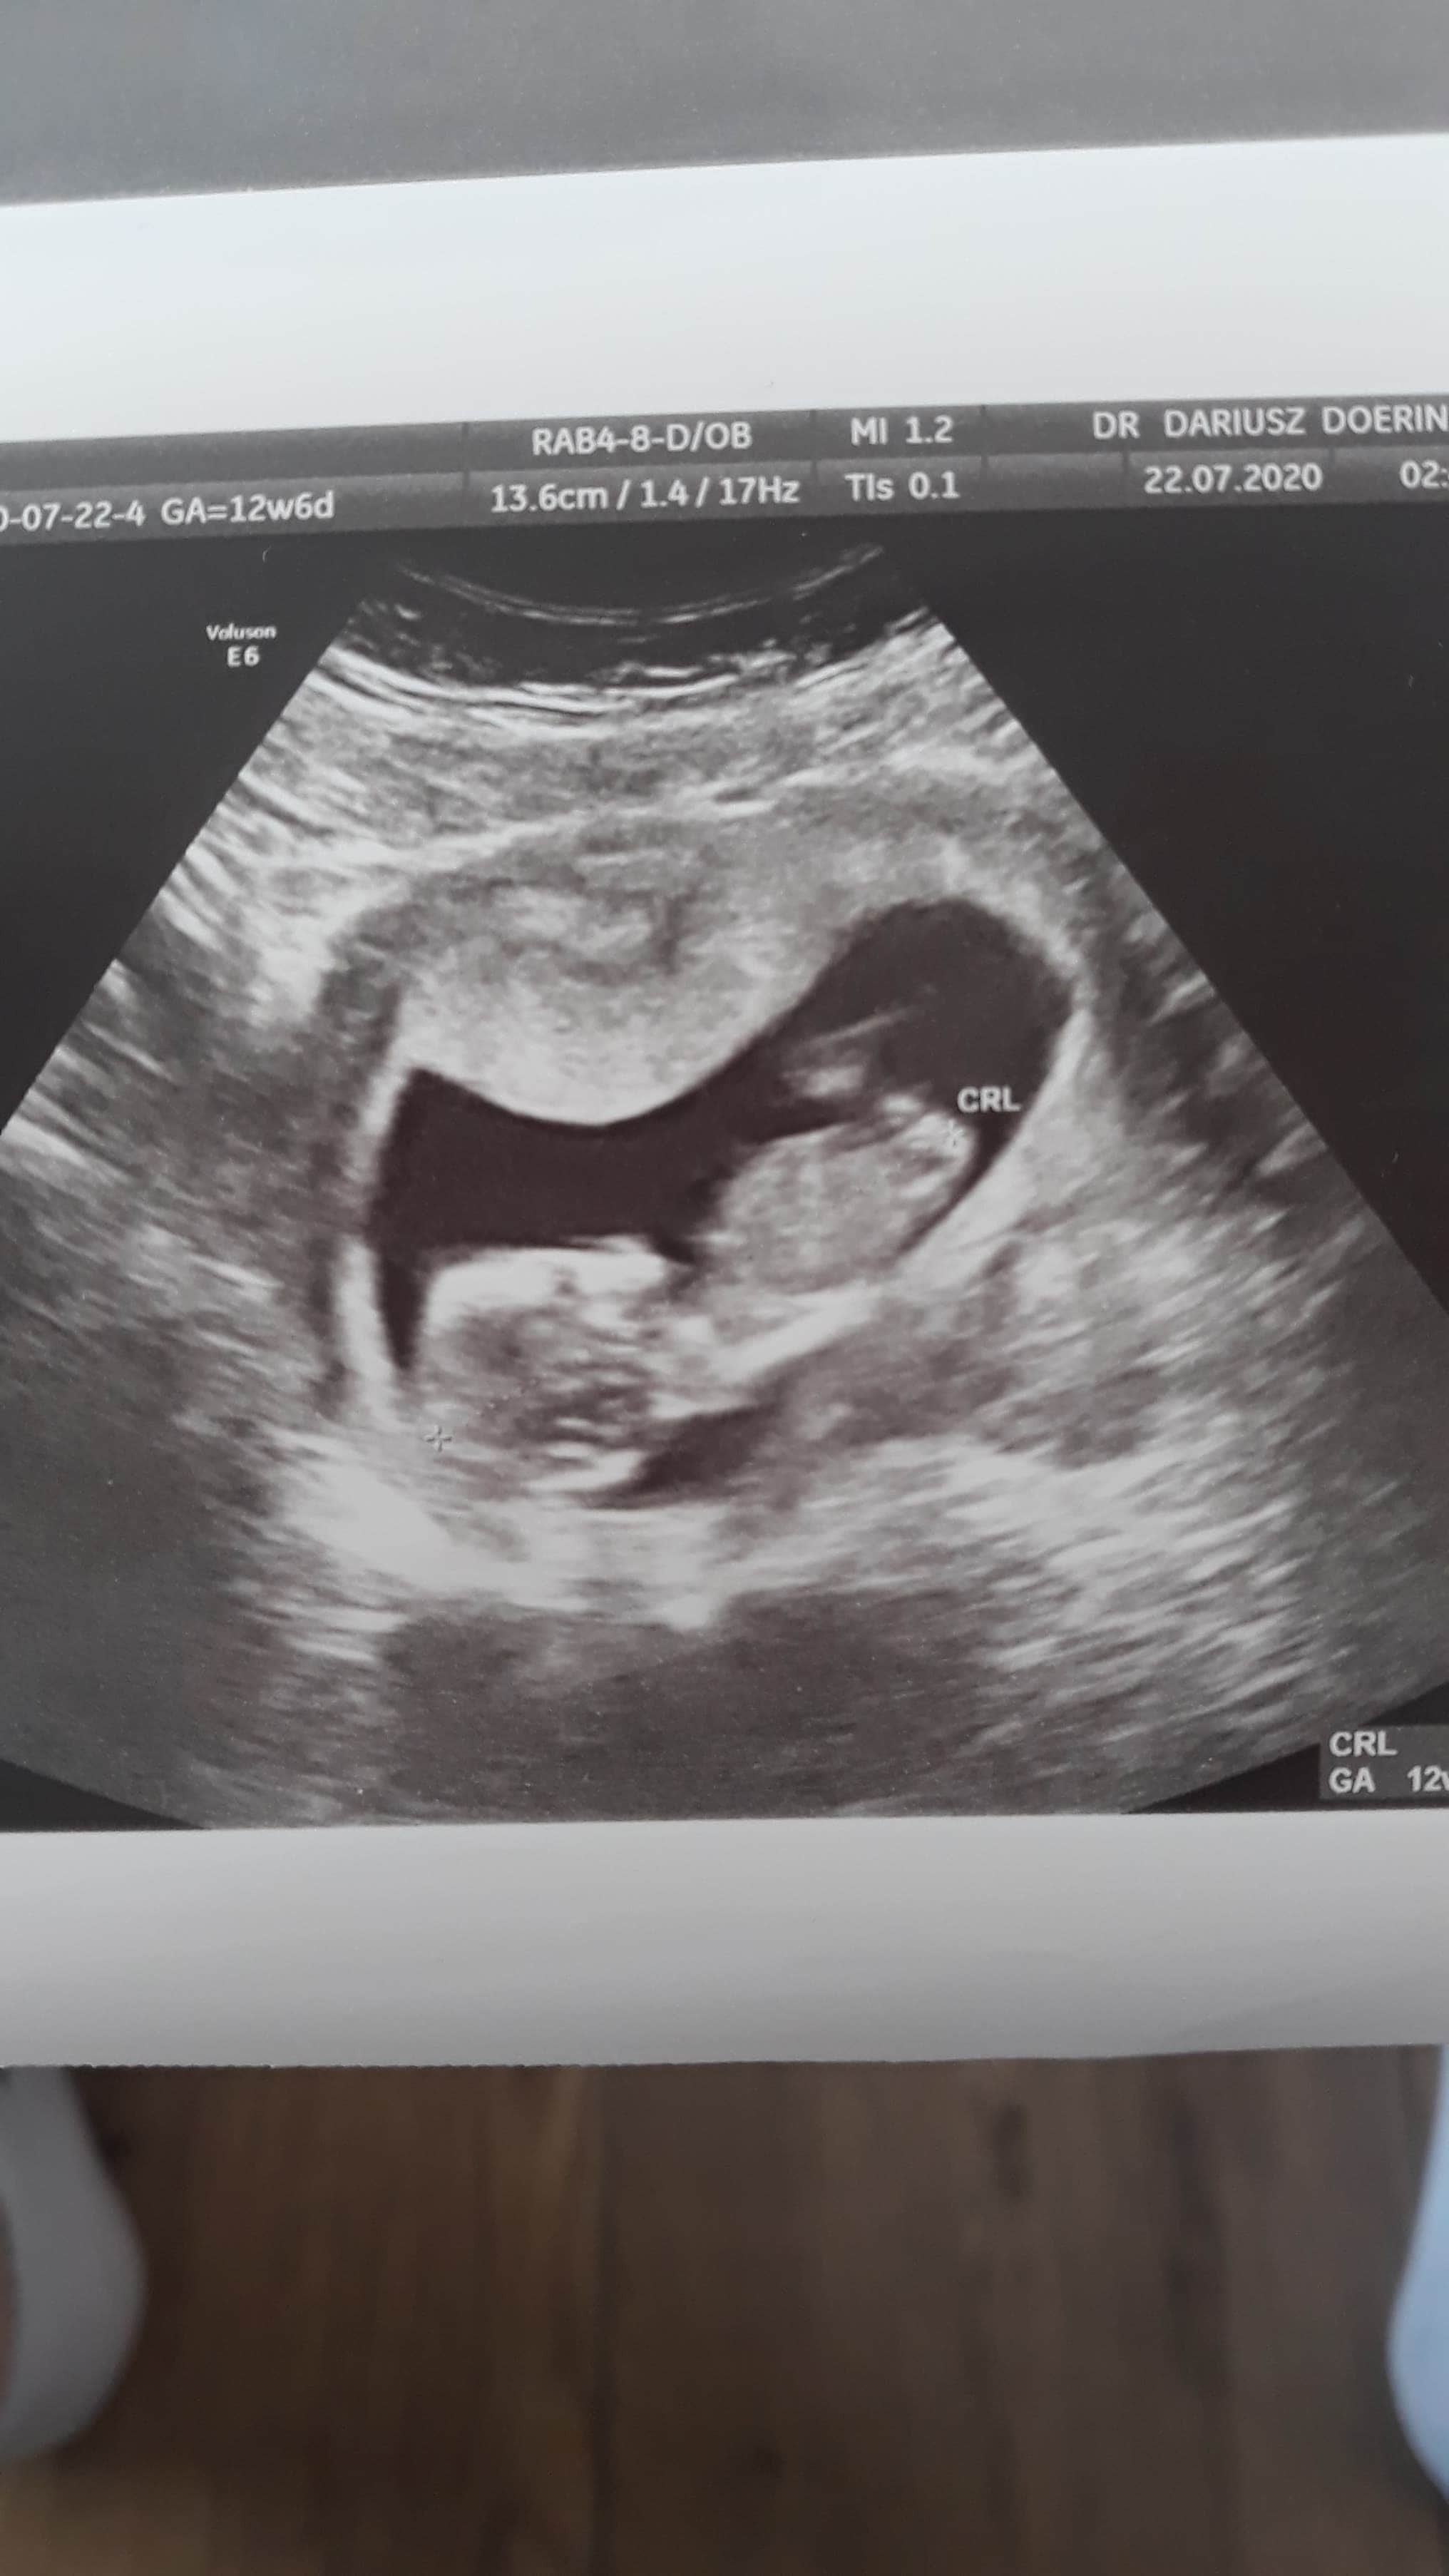

Usg chłopak czy dziewczynka

Witam w 19 tygodniu ciąży dowiedziałam się ze będę miała dziewczynkę w 20 tyg okazało się jednak , że to chłopak. Sama już nie wiem bo na jednym usg widać na pewno dziewuche a na drugim chłopca. Może to pempowina ?? Może ktoś mi pomoże rozwiązać ta zagadkę

Załączniki

• 4A8F5FF1-76CA-4DE0-AC12-5EDF08E820F2.jpg

4A8F5FF1-76CA-4DE0-AC12-5EDF08E820F2.jpg

596,4 KB · Wyświetleń: 44 122